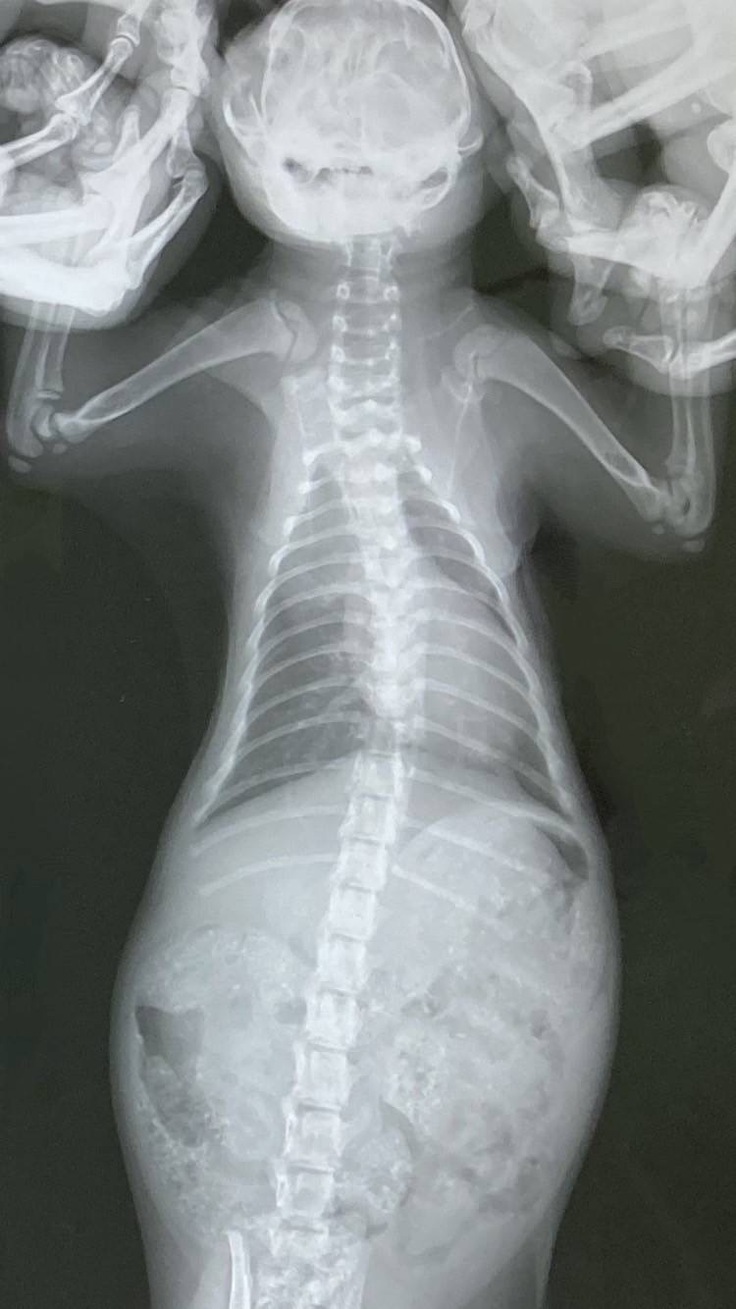

子猫ちゃんたちの通院日で診察とレントゲンを撮ってもらいました。体重が2匹とも900gで標準よりも少し大きいぐらいだと言われました。肺炎は分かりにくいけれど、少しずつ良くなっていると思う、ナイトの漏斗胸も良くなってきているから軽度のままでいけるのではないかと嬉しいお言葉をいただくことが出来ました。